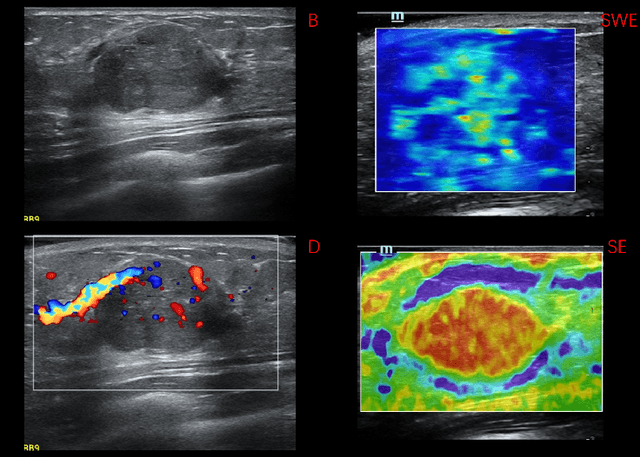

Abstract:Breast cancer is the most common invasive cancer in women. Besides the primary B-mode ultrasound screening, sonographers have explored the inclusion of Doppler, strain and shear-wave elasticity imaging to advance the diagnosis. However, recognizing useful patterns in all types of images and weighing up the significance of each modality can elude less-experienced clinicians. In this paper, we explore, for the first time, an automatic way to combine the four types of ultrasonography to discriminate between benign and malignant breast nodules. A novel multimodal network is proposed, along with promising learnability and simplicity to improve classification accuracy. The key is using a weight-sharing strategy to encourage interactions between modalities and adopting an additional cross-modalities objective to integrate global information. In contrast to hardcoding the weights of each modality in the model, we embed it in a Reinforcement Learning framework to learn this weighting in an end-to-end manner. Thus the model is trained to seek the optimal multimodal combination without handcrafted heuristics. The proposed framework is evaluated on a dataset contains 1616 set of multimodal images. Results showed that the model scored a high classification accuracy of 95.4%, which indicates the efficiency of the proposed method.